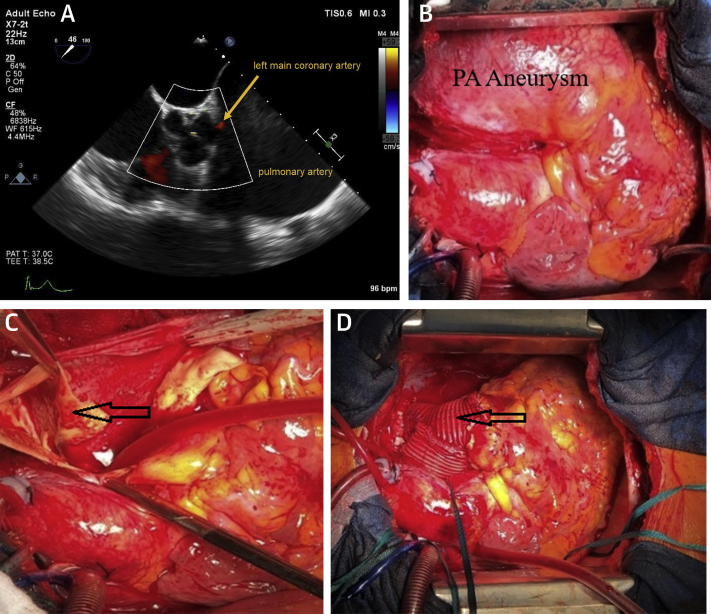

Because the patient was in cardiogenic shock secondary to ST-segment elevated myocardial infarction, after emergency multidisciplinary consultation, salvage surgery was indicated. Intraoperative transesophageal echocardiography confirmed these findings, inclusive of reduced flow in the left main coronary artery. Replacement of the main and right pulmonary arteries with a T-shaped 28-mm prosthetic vascular graft was carried out on cardiopulmonary bypass with beating heart (Figure 2A: flow in left main coronary artery; Figures 2B and 2C: pre-operative; and Figure 2D: post-surgery). At completion of the procedure, transesophageal echocardiography confirmed only mild pulmonary insufficiency. She required extracorporeal life support with veno-arterial extracorporeal membrane oxygenation with peripheral cannulation due to left ventricular failure.

Figure 2.

The Sequence of Surgical Treatment

(A) Intraoperative transesophageal echocardiography view of left main coronary artery flow. (B) intraoperative view of main pulmonary artery (PA) aneurysm. (C) Membrane dissection (arrow). (D) Surgical reconstruction: main and right pulmonary vascular grafts.